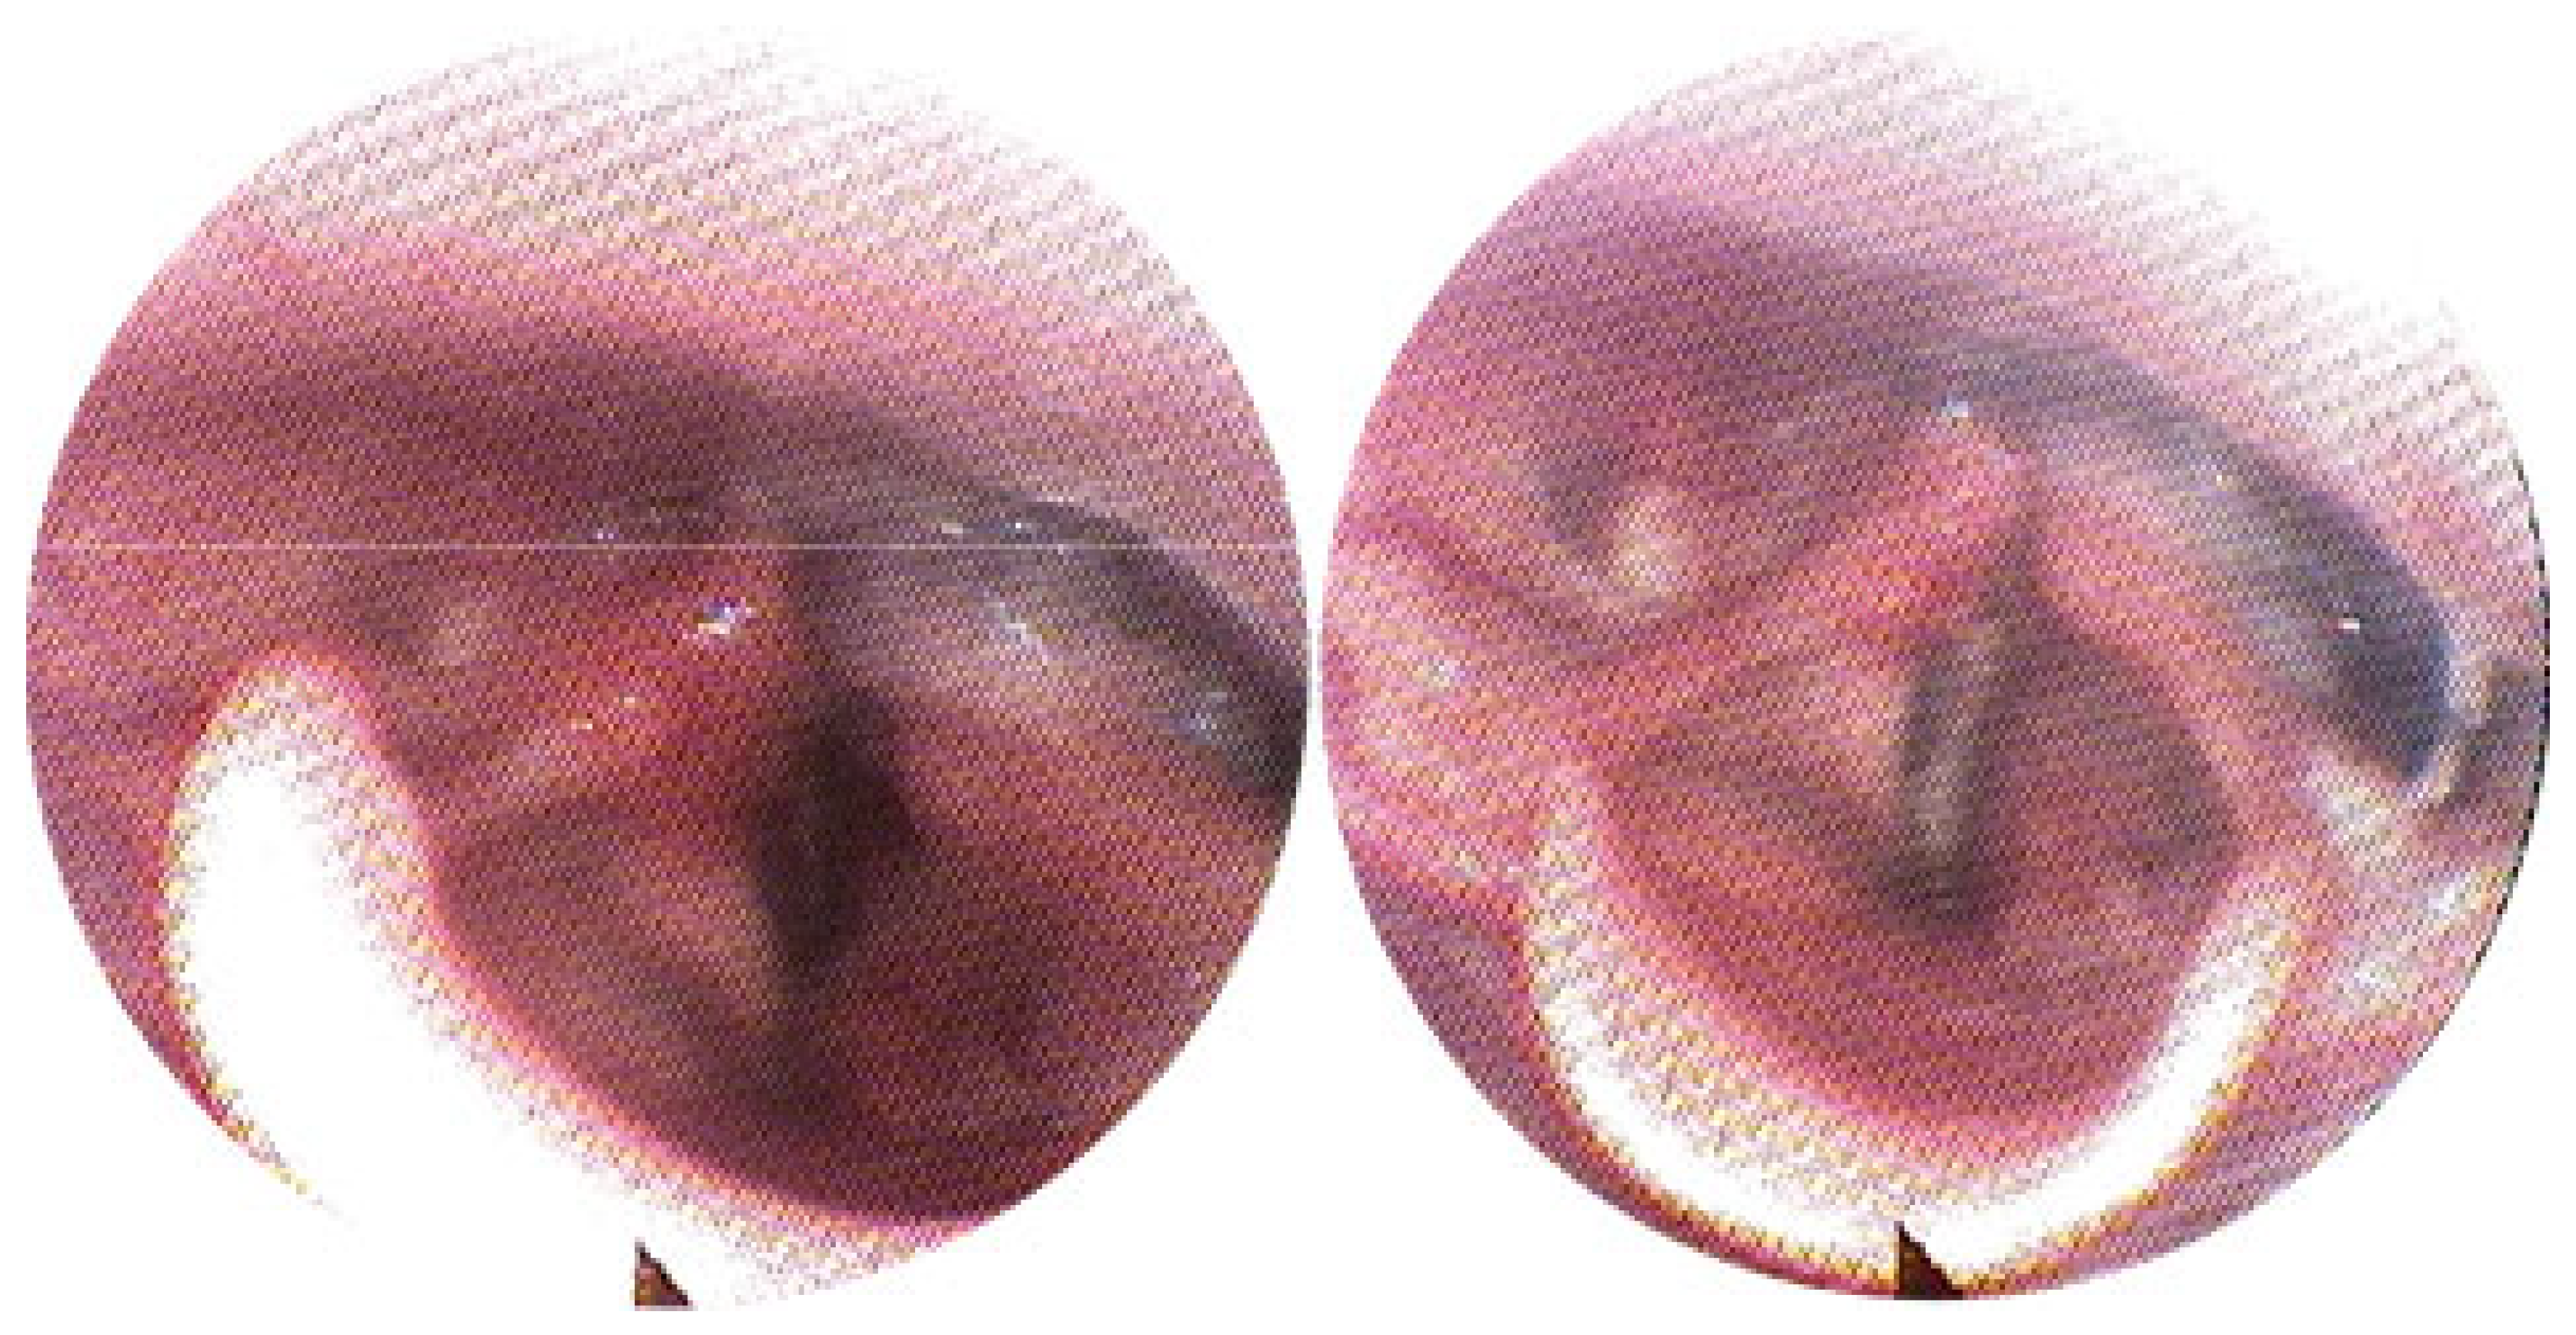

3.2. Clinical Outcomes

| 9 | M | 9 | Oropharynx | 6 | 7334 | 3091 | Significant reduction (>50%) | None |